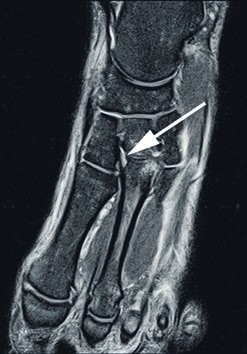

- Die Grad-I-Verletzung umschreibt eine Distorsion des Lisfranc-Bandes ohne mechanische Instabilität. Pa tienten mit dieser Verletzung klagen über Schmerzen in der Region des dorsalen Lisfranc’schen Bandes. Die Röntgenaufnahmen unter Belastung zeigen einen unauffälligen Befund. Kernspintomografisch lässt sich eine Signaländerung im Lisfranc-Bandkomplex nachweisen (siehe Abb. 2), jedoch keine Kontinuitätsunterbrechnung. Im 3‑Phasen-Skelettszintigramm zeigt sich eine Mehranreicherung 19 20.

Die dorsalen und plantaren Anteile des Lisfranc-Bandkomplexes lassen sich kernspintomografisch gut und präzise darstellen (Abb. 6) 28. Wichtig für die Praxis erscheint in diesem Zusammenhang die enge Zusammenarbeit zwischen Radiologen und Orthopäden, denn nur eine akkurate und symptomorientierte Durchführung des Schnittbildverfahrens ermöglicht die entsprechende Darstellung der Bandverletzung mit der gewünschten diagnostischen Sicherheit 29. Bei einer Standardabbildung des Vorfußes im MRT werden die Lisfranc-Bänder oft nicht exakt dargestellt, was eine Aussage zum Ausmaß der Verletzung problematisch macht. Zur exakten Darstellung von knöchernen Verletzungen bietet das Computertomogramm die beste Aufiösung 30.

Bei Athleten tritt eine Verletzung des Lisfranc-Bandkomplexes typischerweise auf, wenn der Fuß bei gleichzeitiger Plantarflexion und leichter Rotation axial belast et wird 43 44. Die Zerreißung des Lisfranc-Bandkomplexes führt zu einer tarsometatarsalen Dehiszenz mit Dislokation der Metatarsale-II-Basis nach dorsal 45. Nunley und Vertullo (2002) 46 gehen in ihren Untersuchungen davon aus, dass es bei der Grad-I-Verletzung lediglich zu einer Distorsion des Lisfranc’schen Bandes in Verbindung mit einer Verletzung der Gelenkkapsel kommt. Aufgrund des in sich noch stabilen Kapselbandkomplexes finden sich normale Belastungsaufnahmen; die Verletzung der dorsalen Bandanteile lässt sich jedoch kernspintomografisch nachweisen 47. Bei der Grad-II-Verletzung kommt es zusätzlich zu einer vollständigen Zerreißung der dorsalen Bandanteile. Radiologisch zeigt sich dies durch das Auseinanderweichen von Os metatarsale I und II auf den Röntgenaufnahmen unter Belastung. Da die plantaren Kapselbandanteile intakt bleiben, kommt es jedoch zu keinem Absinken des Längsgewölbes in der Seitenaufnahme. Bei Grad-III-Verletzungen liegt eine komplette Zerreißung der dorsalen und plantaren Kapselbandstrukturen mit einem instabilen ersten Tarsometatarsalgelenk vor. Dies zeigt sich radiologisch durch ein Absinken des Längsgewölbes 48.